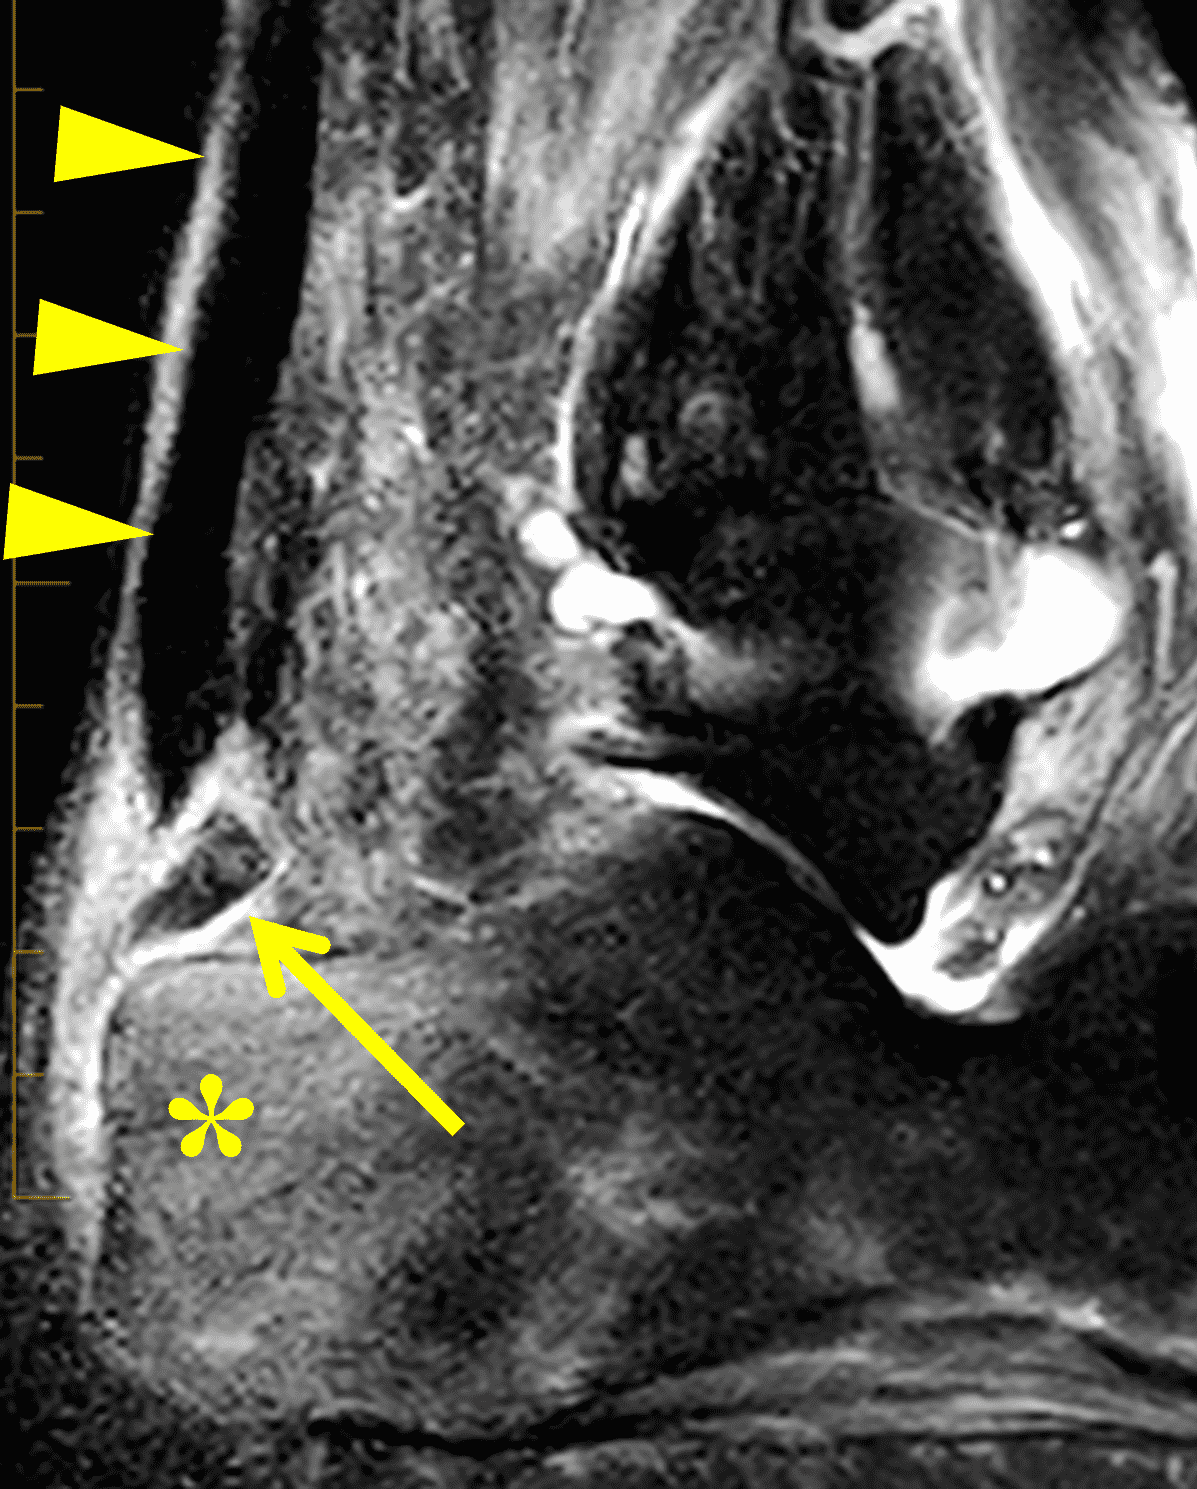

Figure 2: Complete Achilles tendon rupture. (2A) The lateral radiograph shows a thick and indistinct proximal Achilles tendon contour (arrows). (2B) A fat-suppressed T2-weighted image shows complete rupture of the tendon with a fluid-filled gap (yellow arrow) measuring 1.5 cm in length, located 10 cm cranial to the tendon insertion (blue arrow) and just distal to the edematous myotendinous junction (red arrow). The tear is superimposed on diffuse tendinosis. (2C) A sagittal T1-weighted image confirms the diffuse tendinosis. Fluid extends anteriorly into Kager’s fat pad (arrow) suggesting disruption of the anterior paratenon. (2D) A transverse fat-suppressed T2-weighted image through the proximal tendon shows no intact fibers (arrow), confirming the full-thickness rupture.